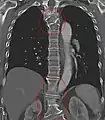

Congenital block vertebra of the lumbar spine. CT volume rendering.